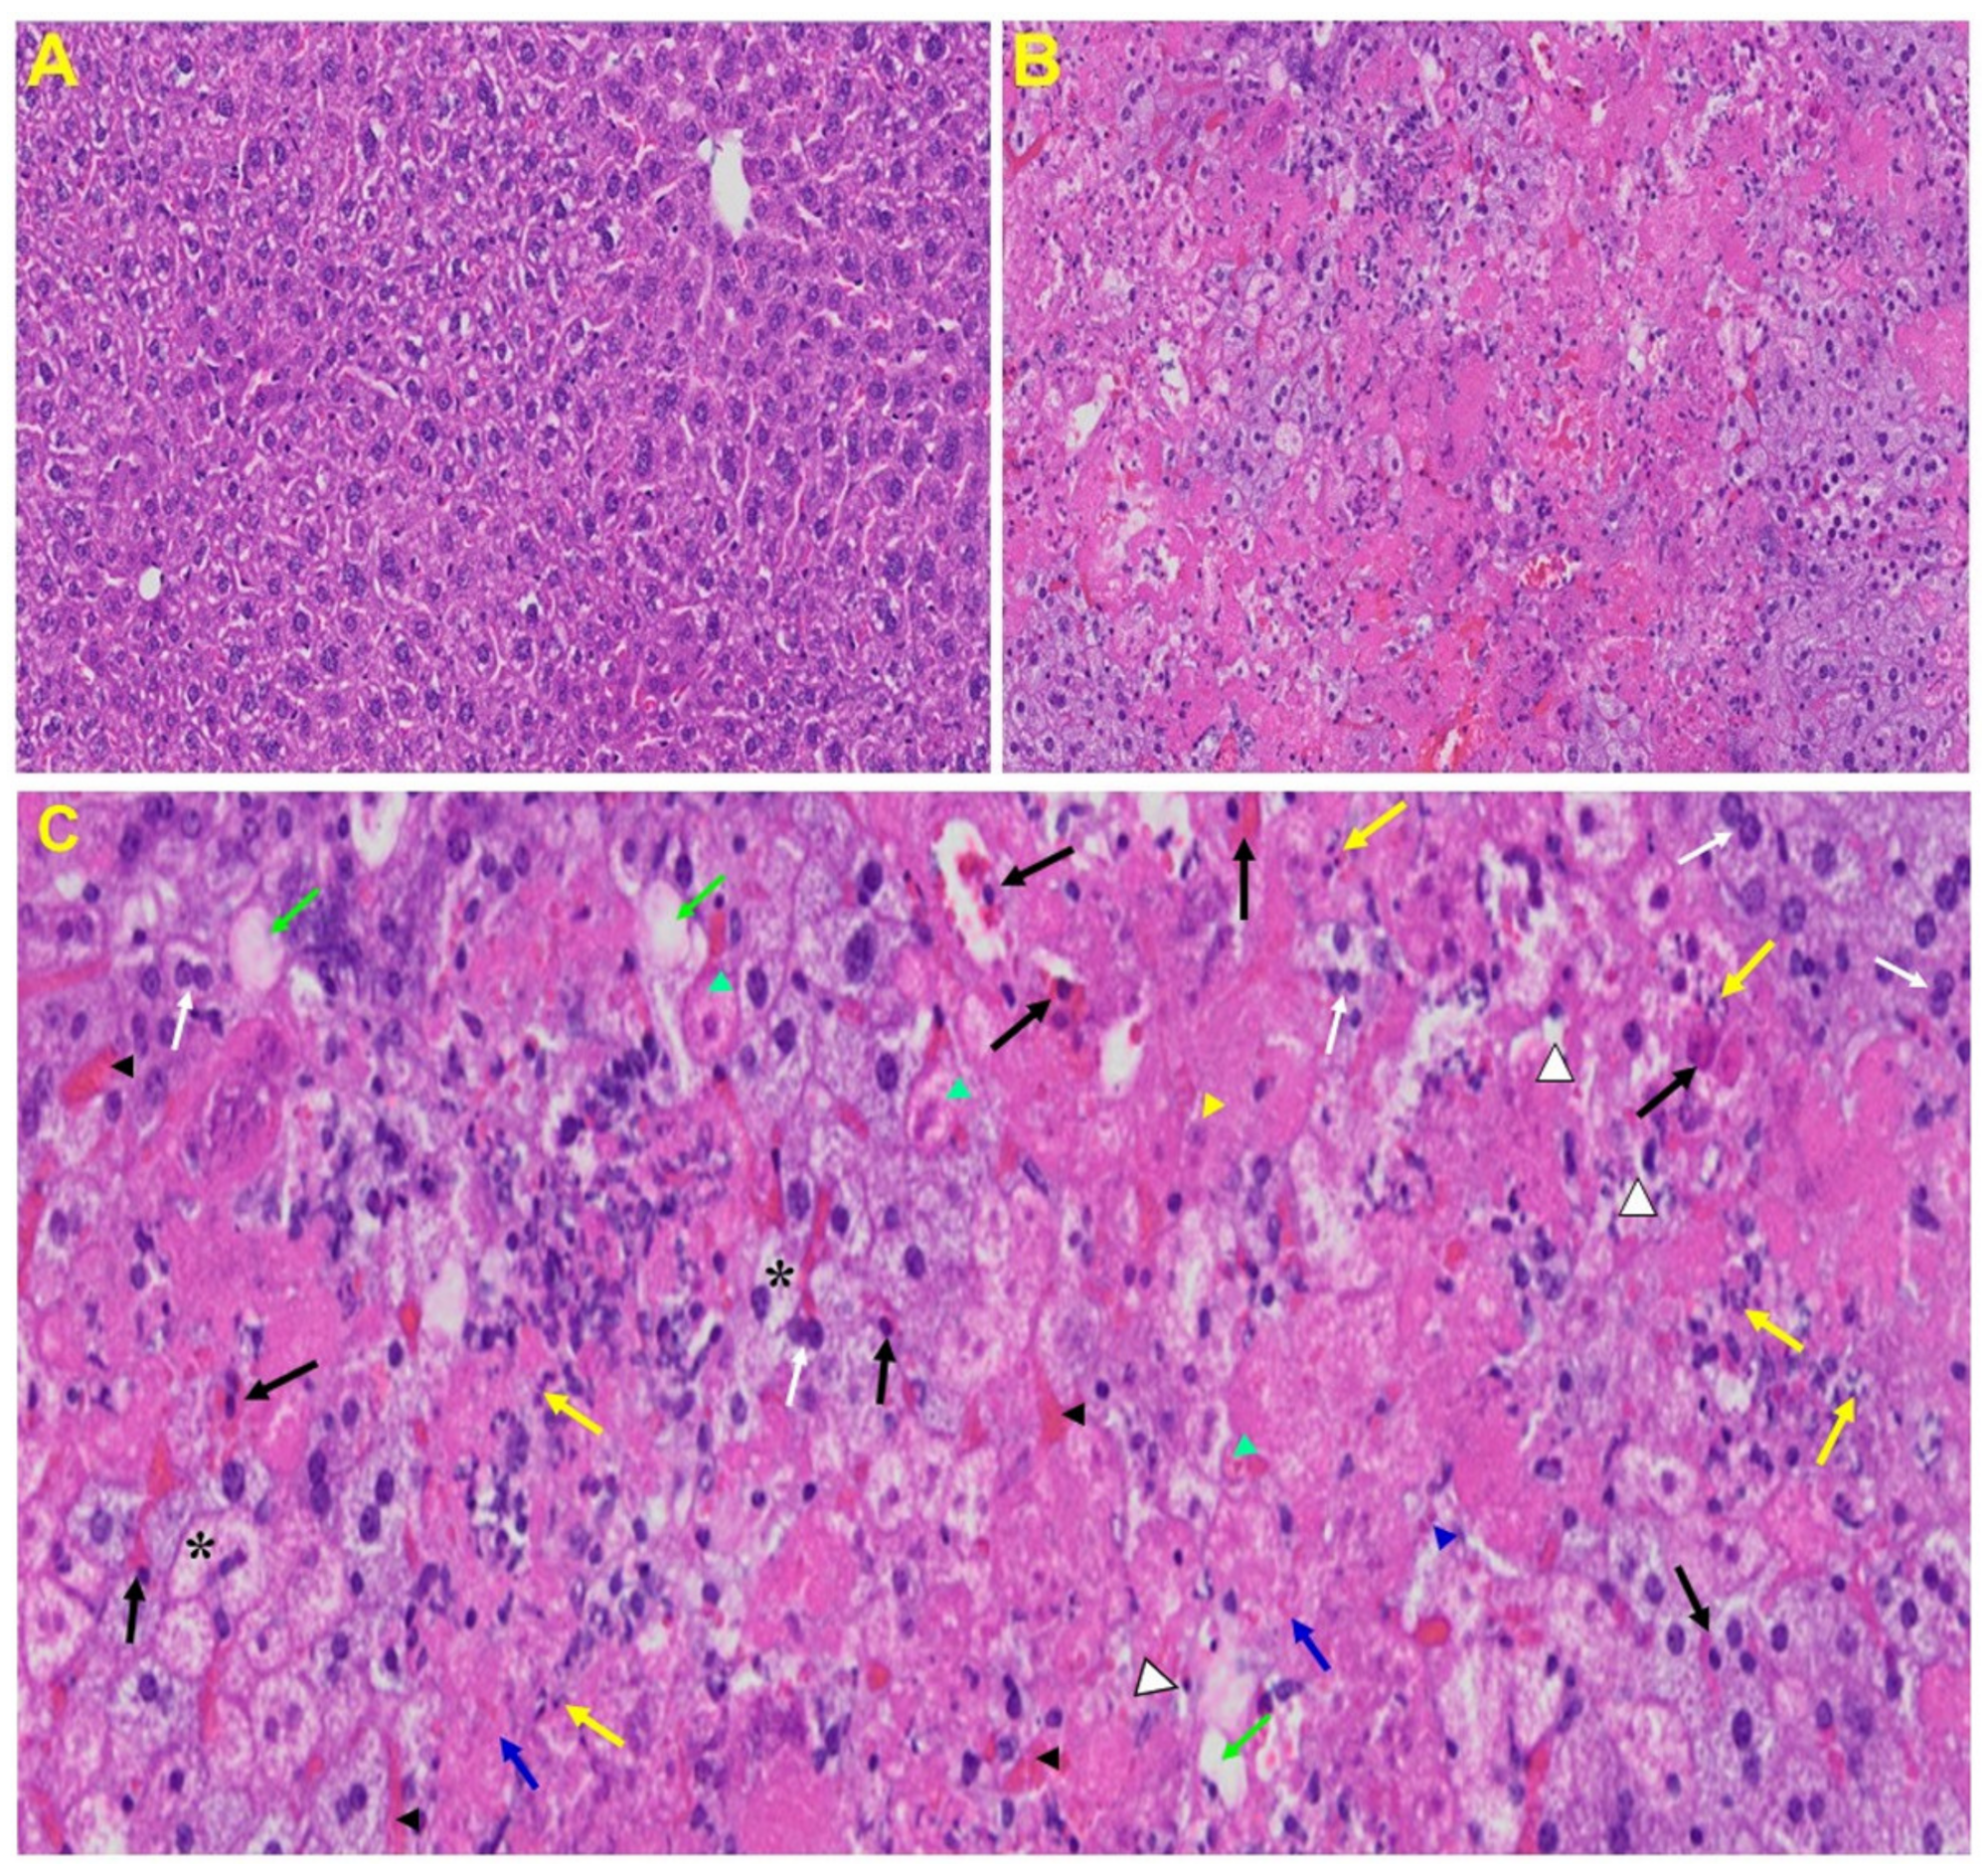

3.3. Histopathological Changes Post-MHV-1 Infection